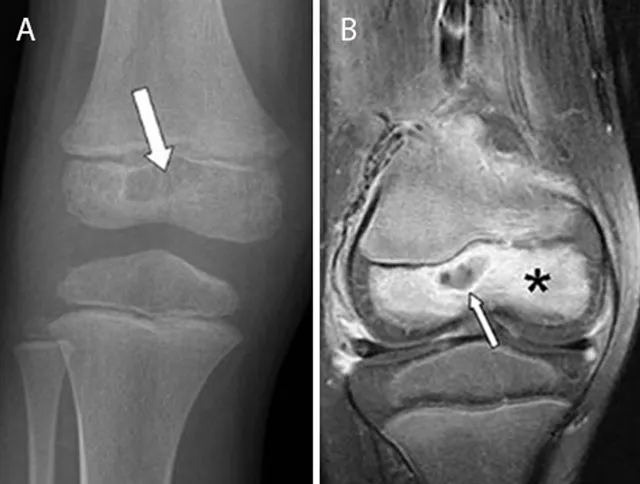

- X-ray: Early changes subtle (10-14 days); later: periosteal reaction, sequestrum.

- MRI: Gold standard for early detection; shows marrow edema, abscess.

- Brodie's Abscess: Chronic, localized intraosseous abscess. X-ray: lucent nidus, sclerotic rim. Tibia common.